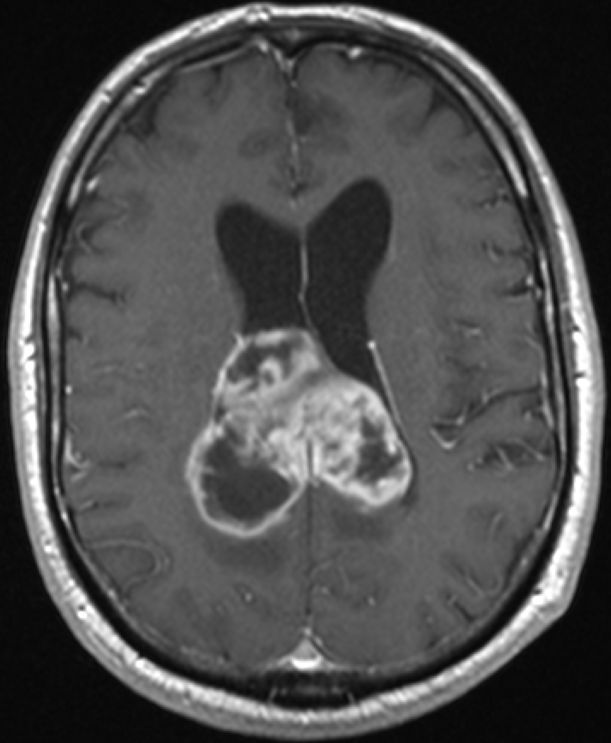

Zystisches Gliom parieto-occipital |

![]() |

![]() | ||